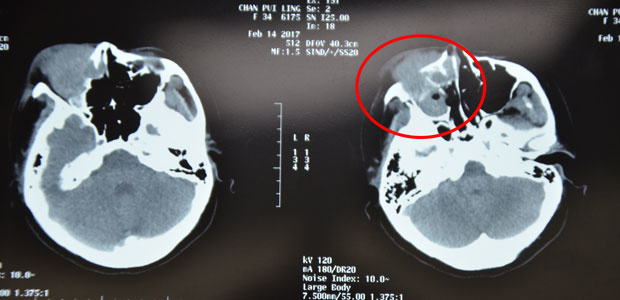

Before treatment and after the first interventional therapy

In Feb. before treatment, masses filled her nasal and sinus cavities and her right eyeball was pressed to displace.

In March, after treatment, masses in her nasal and sinus cavities reduced and basically returned to a normal stage and her right eyeball back to the position.